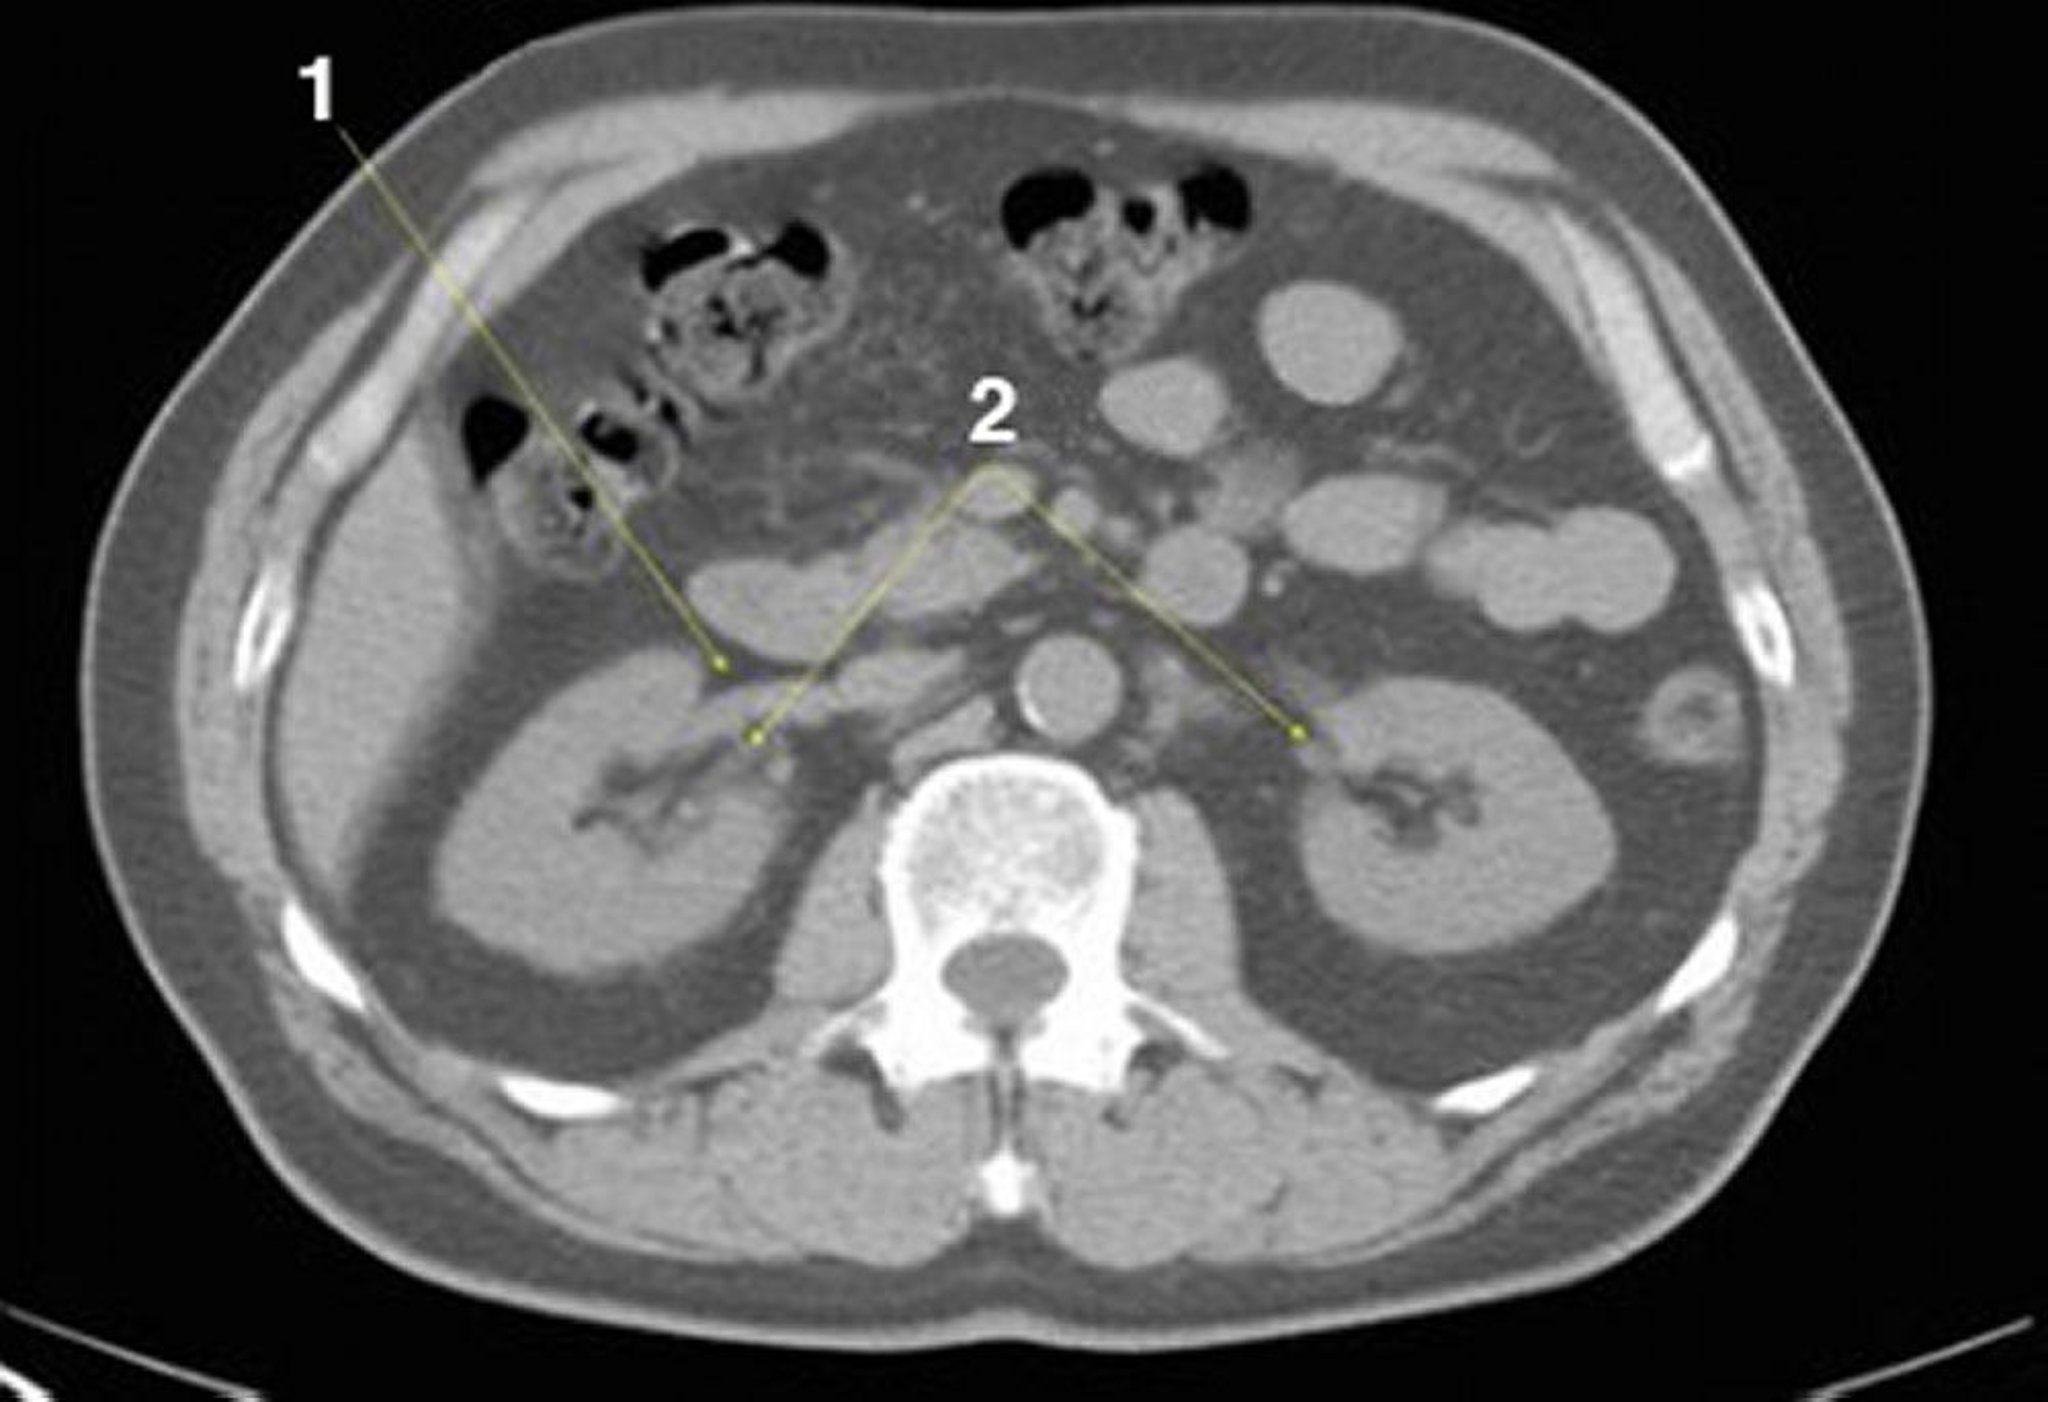

CT-Scan von Abdomen und Becken mit normaler Anatomie ohne Kontrastmittel (Folie 14)

1 = rechte Nierenvene; 2 = Nierenhilus.